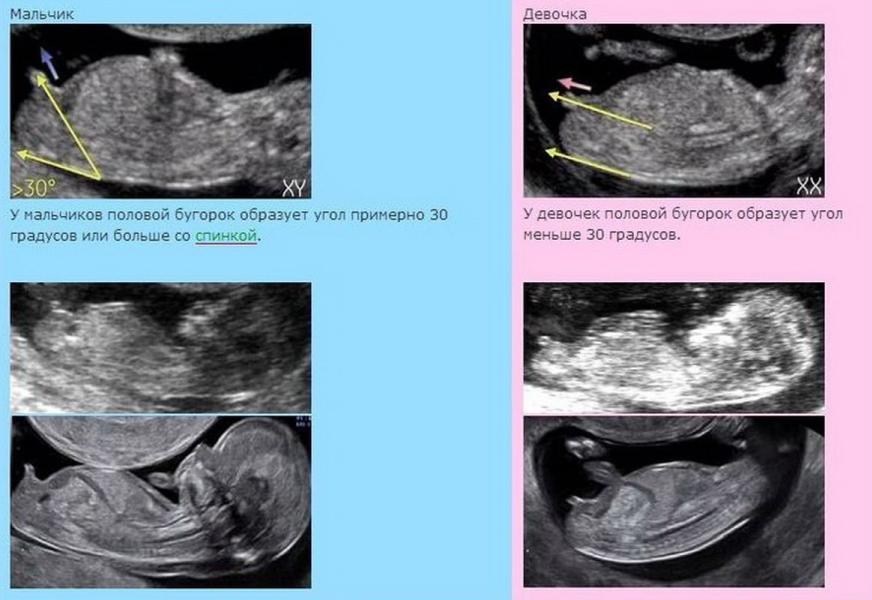

В интернете почитала, что вероятность ошибок очень велика, стала читать дальше и поняла, что, видимо не зря 😄 (см.фото)